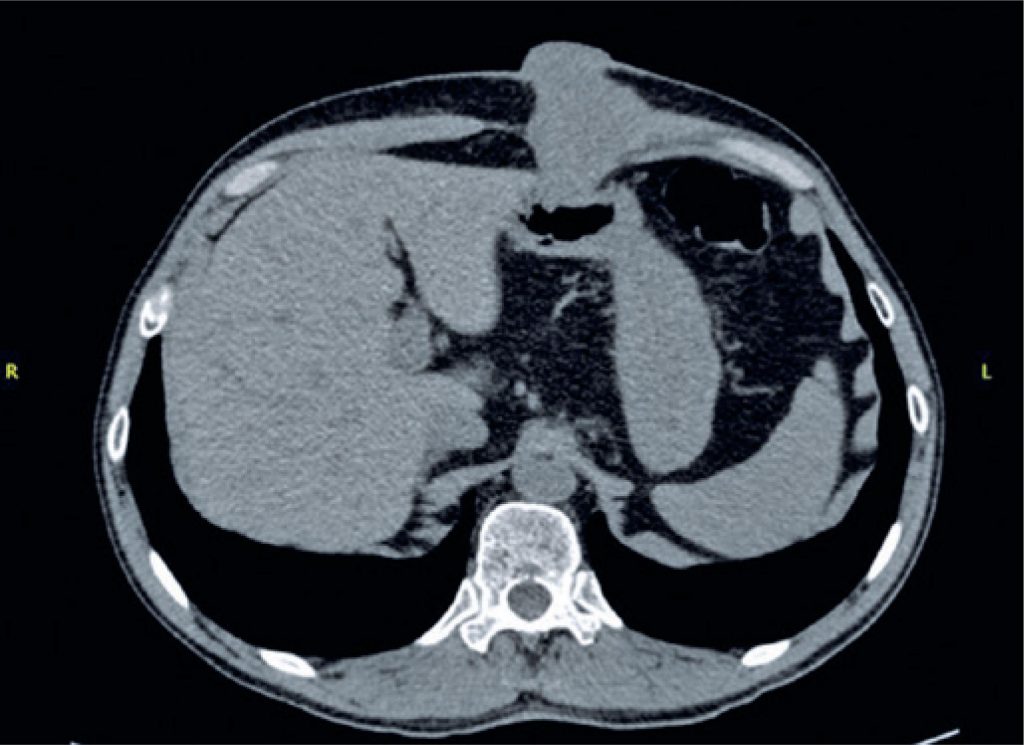

A gastrostomia endoscópica percutânea é utilizada para oferecer suporte nutricional enteral para pacientes com neoplasias obstrutivas de orofaringe ou esôfago. A colocação da sonda é considerada segura, com poucas complicações. Apesar disso, uma complicação em particular, considerada rara, está sendo cada vez mais descrita na literatura: a metástase de neoplasia de cabeça e pescoço para o estoma da gastrostomia. Neste relato, descrevemos um caso de metástase de carcinoma espinocelular de laringe para o sítio da gastrostomia, e discutimos as possíveis etiologias e alternativas, buscando diminuir a incidência desta complicação.